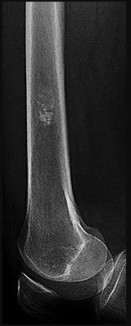

Figures 7a through 7d are the radiograph, MR images, and biopsy specimen of a 35-year-old man who has a painful, slowly enlarging knee mass. Which chromosomal translocation is characteristic of this pathology?

Synovial sarcoma is a soft-tissue sarcoma that usually occurs in young adults. Synovial sarcoma often causes pain, unlike most soft-tissue sarcomas, which generally do not cause pain. Imaging characteristics include soft-tissue calcifications on plain radiographs and a heterogeneous mass that is generally isointense to muscle on T1-weighted images and hyperintense to muscle on T2-weighted images. There are biphasic and monophasic types of synovial sarcoma. The biphasic

type, which is depicted here, has both spindle cell and epithelial components and will stain for both vimentin and cytokeratin. More than 90% of patients with synovial sarcoma have a characteristic genetic translocation of t(X;18), which results in the fusion protein SS18-SSX. This translocation can be stained for use of florescence in situ hybridization technology. t(11;12) is seen in Ewing sarcoma. T(9;22) is seen in extraskeletal myxoid chondrosarcoma. t(12;16) is seen in myxoid liposarcoma.